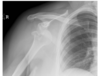

5

Q